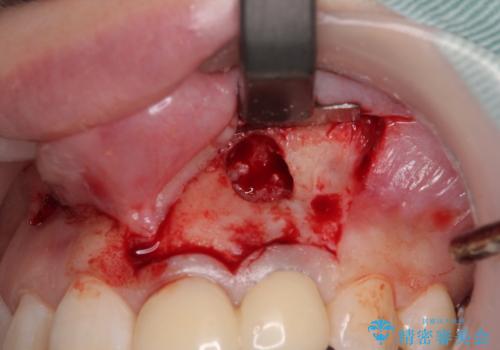

以前歯根端切除術を受けているものの、現在の主流とは異なる術式で行われているため、再度歯根端切除術を行うこととしました。

痛みが改善したことを確認した上で、オールセラミッククラウンにて補綴治療を行うこととしました。

歯根端切除から2週間を経過した時点で痛みは全くなくなっており、処置から6ヶ月後に撮影したレントゲン写真では炎症で吸収していた骨が回復している様子が確認されました。